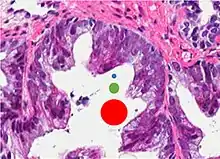

77%[notes 2] | 54%[notes 2] | ![]() |

Microscopic characteristics

- Specific but relatively rare

- [notes 4]

- Collagenous micronodules[4]

- Glomerulations,[4] epithelial proliferations into one or more gland lumina, typically a cribriform tuft with a single attachment to the gland wall.[18]

- Perineural invasion.[4] It should be circumferential[18][notes 5]

- Angiolymphatic invasion[4]

- Extraprostatic extension [4]

Glomerulation.

- Relatively common and highly specific

- [4]

- Multiple nucleoli

- Eccentric nucleoli[4]

Acinar adenocarcinoma with multiple nucleoli.

Acinar adenocarcinoma with double and eccentric nucleoli.

- Less specific findings.

- Mitoses (also seen in for example high-grade prostatic intraepithelial neoplasia (HGPIN) and prostate inflammation).[4]

- Prominent nucleoli[4]

- Intraluminal eosinophilic secretion[4]

- Intraluminal blue mucin[4]

Adenocarcinoma with two mitoses in reactive epithelium.

Acinar adenocarcinoma with intraluminal blue mucin.